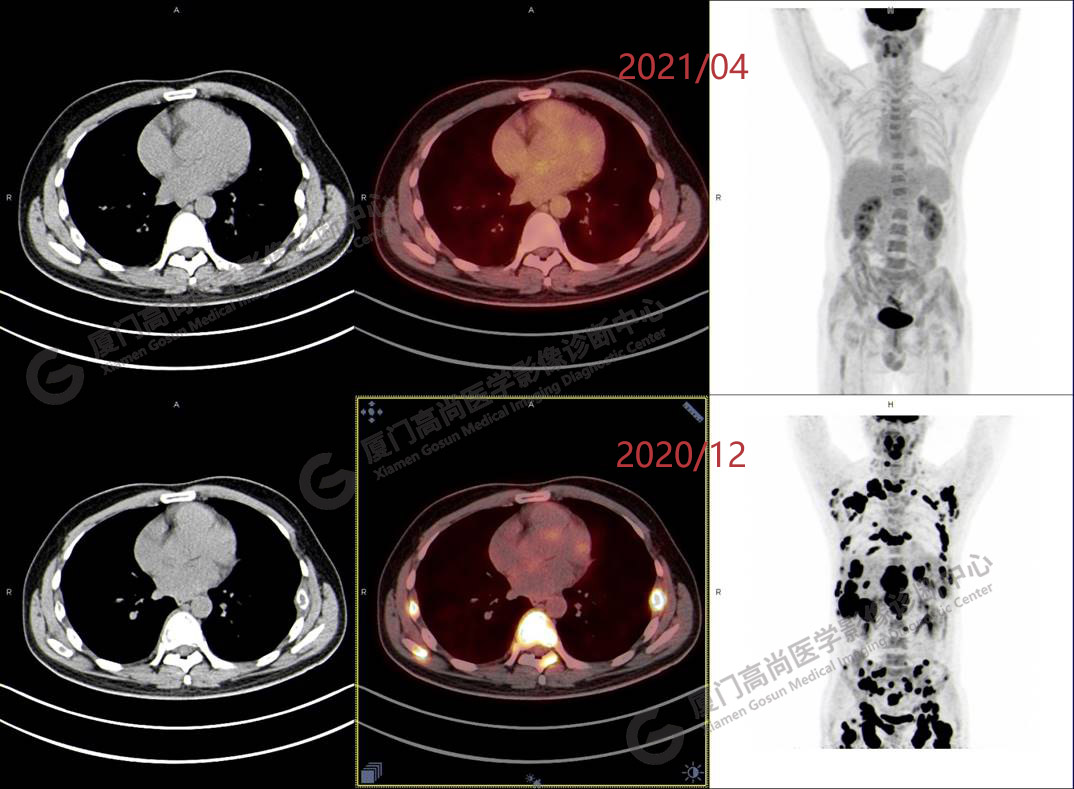

2020.12月本中心PET/CT示:全身多發(fā)腫大淋巴結(jié),代謝不同程度增高;肝臟多發(fā)稍高密度結(jié)節(jié)、脾臟多發(fā)稍低密度結(jié)節(jié),代謝異常增高;全身多發(fā)骨骼溶骨性骨質(zhì)破壞,代謝異常增高,胸2、腰1椎體病理性骨折,診斷為淋巴瘤。隨后,病理確診為彌漫大B細(xì)胞淋巴瘤。

患者化療4個療程后,于2021.04月返我中心復(fù)查,現(xiàn)患者本人已能自主行走,此次更是獨自一人來我中心復(fù)查PET/CT。檢查結(jié)果顯示:原全身多發(fā)病灶基本消失,且病灶代謝基本恢復(fù)正常。以下是患者PET/CT前后對比圖像:

圖片PET/CT前后對比圖像3